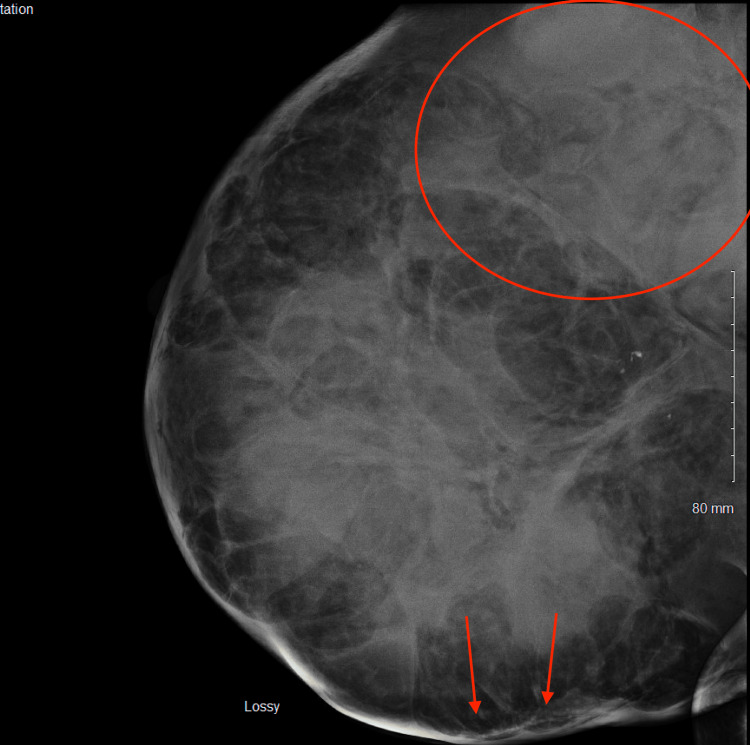

The patient had an urgent bilateral diagnostic mammogram showing an abnormal density throughout the right breast, focally pronounced in the upper outer posterior right breast; a large superficial asymmetry was seen with changes extending to the skin surface (Figure 3). Ultrasound of the right breast showed a large masslike structure measuring at least 5.4cm x 6.8cm x 5.8cm in size and potentially larger. A complete blood count showed a hemoglobin of 6.7. The patient then underwent an ultrasound-guided core biopsy and outpatient packed red blood cell transfusion. Pathology revealed a malignant spindle cell neoplasm. Differential diagnoses included a malignant phyllodes tumor and inflammatory breast cancer.

Figure 3. Diagnostic mammogram showing an abnormal density throughout the right breast, focally pronounced in the upper outer posterior right breast (encircled); a large superficial asymmetry was seen with changes extending to the skin surface (arrows).